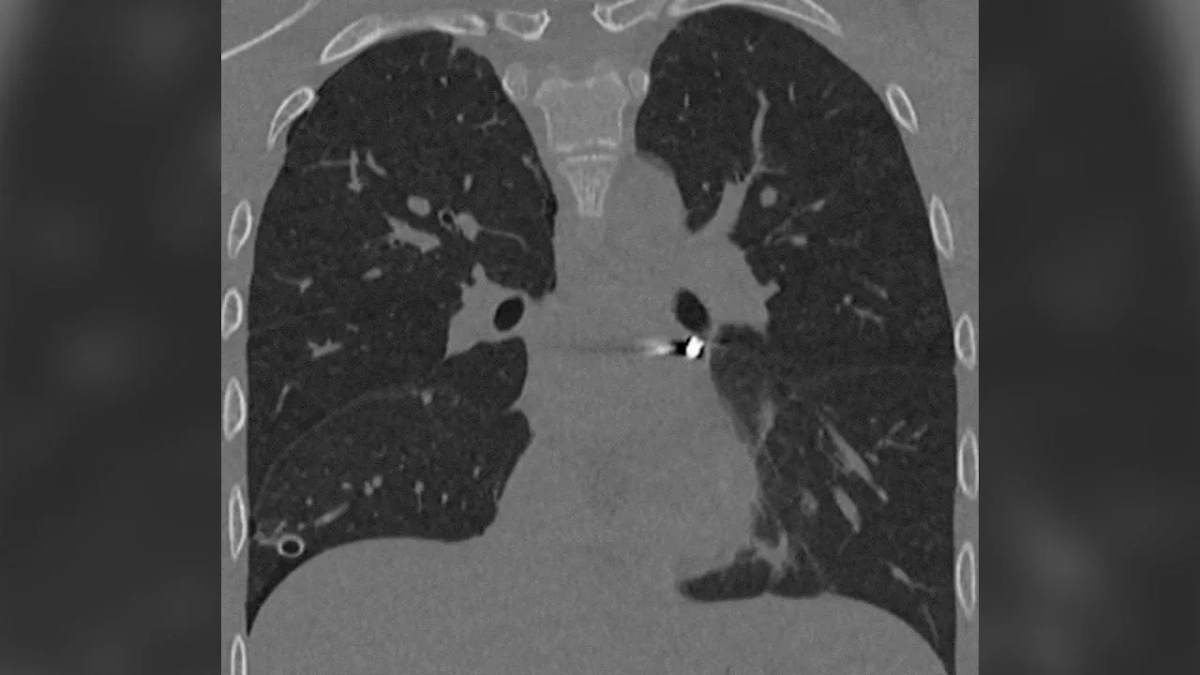

Медицинское обследование показало, что пуля проникла в грудную клетку и оказалась в непосредственной близости от сердца, а именно в полости перикарда, что представляло серьёзную угрозу для жизни пациента и требовало немедленной операции. В итоге хирургическое вмешательство прошло успешно, состояние подростка стабилизировалось, и он был выписан из больницы.

«Инородное тело мигрировало в опаснейшую зону — между лёгочными венами у задней поверхности предсердия. Мы выполнили малоинвазивную операцию со вскрытием перикарда, работая буквально в миллиметрах от жизненно важных структур. Особую сложность представляла необходимость манипулировать инструментами в условиях ограниченного обзора и постоянного движения сердца», — рассказывает заведующий отделением детской хирургии № 2 Никита Степаненко.

В ходе операции медикам удалось извлечь инородное тело без единого разреза.